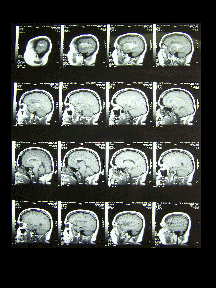

MRI Pre-operation (Craniotomy 17 August 2004) taken at Royal Melbourne 3 August 2004. Images are clickable.